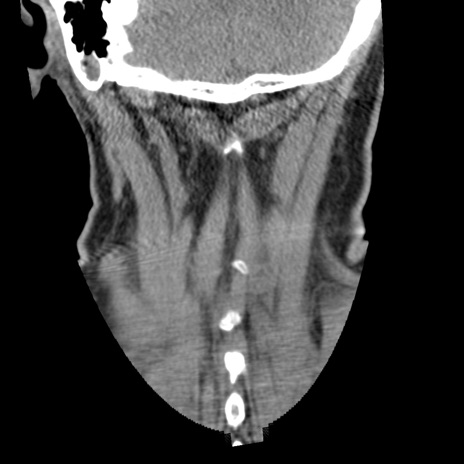

症例50 頚椎CT(冠状断像)

頚椎CT

横断像